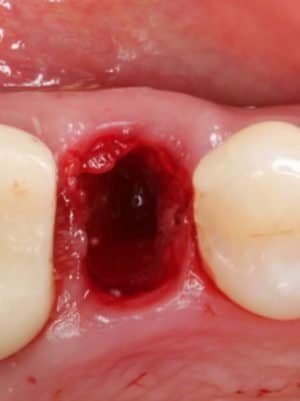

- CLINICAL VIDEO Socket Preservation after a Lower Molar Extraction using an

- Allograft and a d-PTFE Membrane | Dr Sascha A Jovanovic

- CLINICAL VIDEO Immediate Tooth Replacement of Failing Tooth #11 | Dr Sascha A Jovanovic

- CLINICAL VIDEO Immediate Implant Placement in the Esthetic Zone | Dr Robert Silva